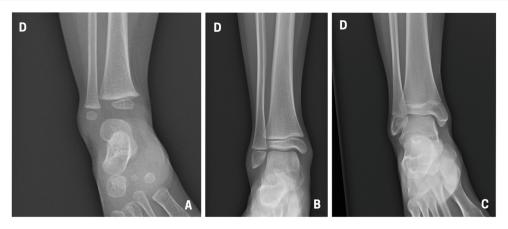

La cheville étant initialement une matrice cartilagineuse qui va progressivement s’ossifier, la lecture des radiographies est parfois difficile chez l’enfant, dont les cartilages de croissance sont encore visibles. A : enfant de 18 mois ; B : enfant de 8 ans ; C : enfant de 15 ans.